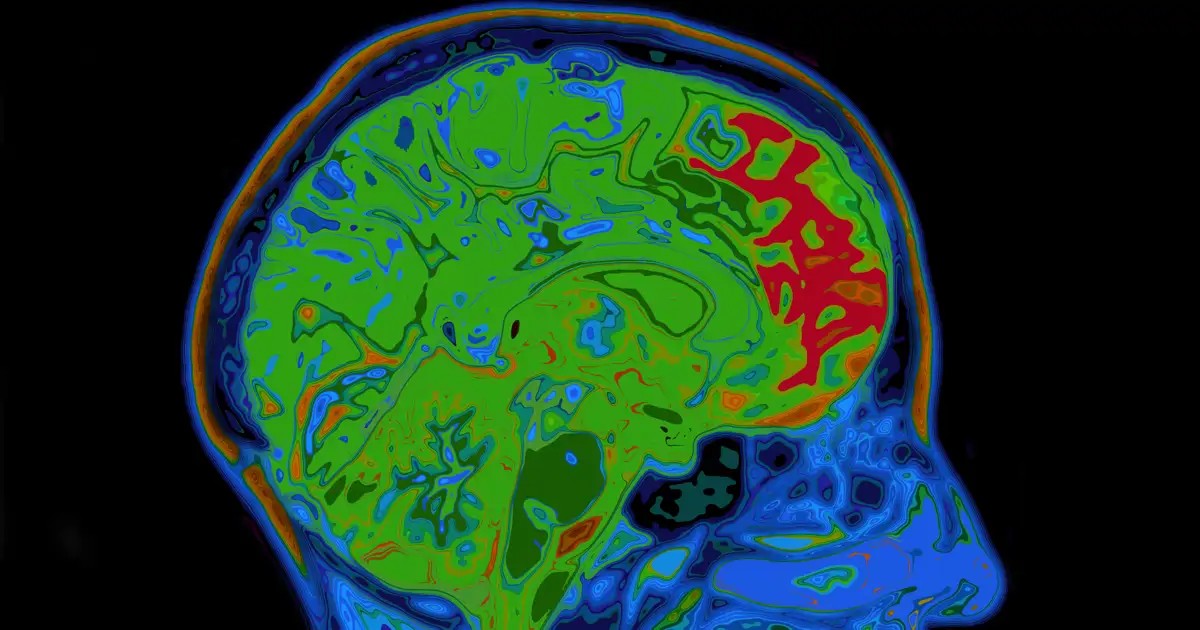

Během výzkumu vědci odhalili zásadní neurobiologický mechanismus, který výrazně ovlivňuje, jak rychle mozek vytváří asociace odměn. Tento mechanismus má vliv nejen na vytváření prospěšných návyků, ale i na rozvoj závislostí. Hlavní roli zde hraje protein KCC2, který funguje jako katalyzátor asociativního učení a v tomto kontextu byl přirovnán k přepínači.

KCC2 je protein důležitý pro homeostázu chloridů v neuronech. Dále moduluje činnost neuronů zodpovědných za segregaci dopaminu, což je neurotransmiter spojený se štěstím. Snížená aktivita tohoto proteinu vede k výraznému nárůstu aktivity dopaminergních neuronů, což rychle umocňuje nové asociace mezi vnějšími podněty a příznivými výsledky.

Tým vědců provedl pozorování na mozkové tkáni myší a pomocí behaviorálních experimentů zjistil, že vztah mezi přítomností KCC2 a citlivostí na učení má inverzní proporci: čím nižší je přítomnost KCC2, tím vyšší je citlivost na učení. Objevili také, že tento protein nejenom reguluje frekvenci aktivace, ale také koordinaci neuronů. To je zásadní, protože synchronizovaná aktivita nervových buněk podporuje větší uvolňování dopaminu.